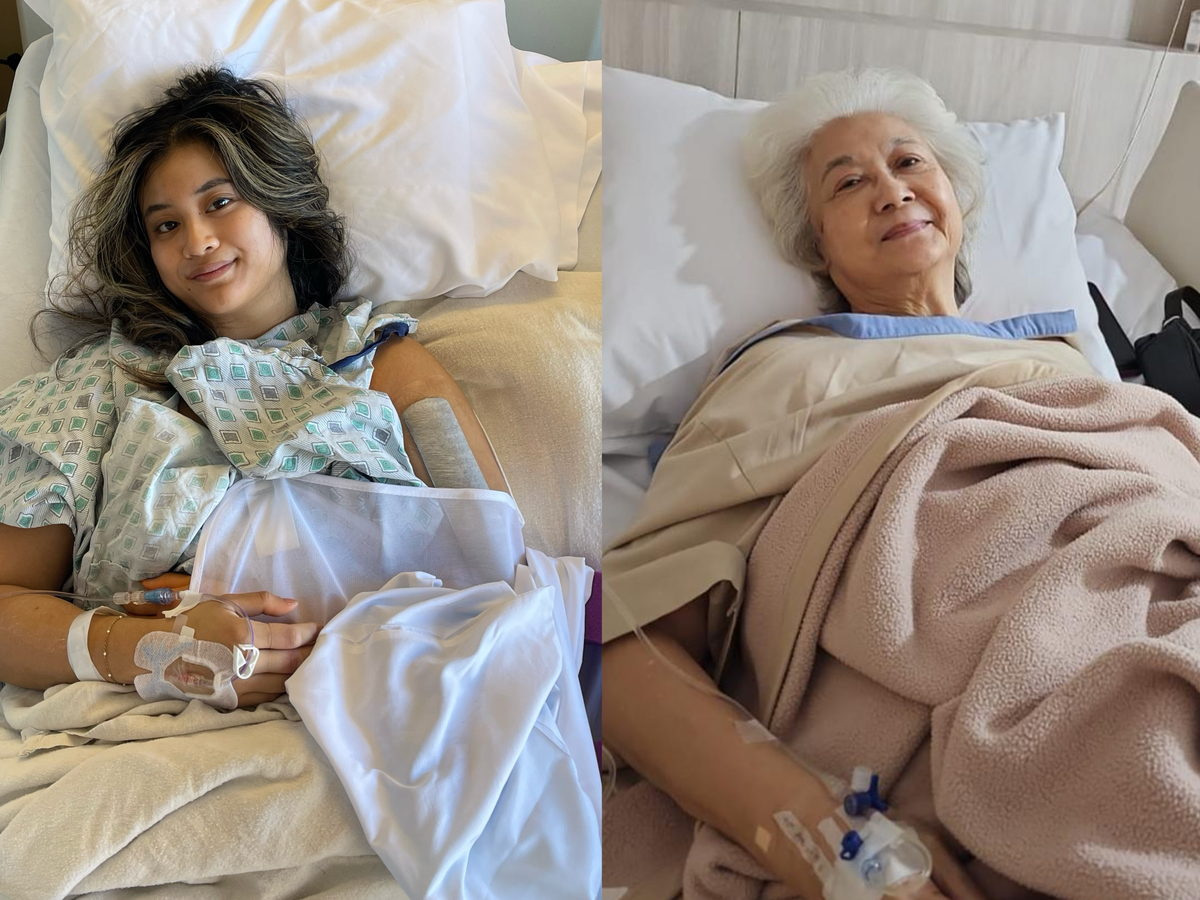

On January 26, my sister fell and broke her arm in New York a few days before our mom was supposed to fly in from Jakarta, Indonesia. On January 28, my grandma fell and broke her leg in Jakarta. Both required surgery and hospitalization.

Torn between her daughter in New York and her mother in Jakarta, it was ultimately decided that my mom would go through with her trip to take care of her daughter while remotely arranging for care for her mother.

My sister and grandma's surgeries were successful but also very costly (especially if we include the extensive physical therapy they would both have to go through). My mom bears the majority of our family's financial responsibilities. She is a single mother who has to work 70+ hours a week to support her family, acting as our grandma's main caretaker and regularly helping both me and my sister when our own income falls short of making rent.